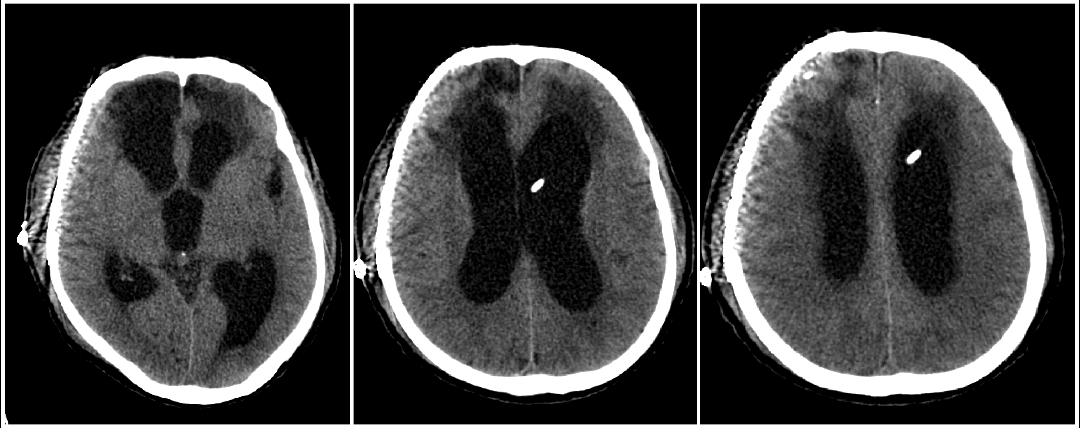

近期陕西省核工业二一五医院神外监护室完成西北首例低颅压性脑积水ProSA+ProGAV系统分流手术。患者老年男性,半年前因重型颅脑损伤在本院行开颅手术治疗,术后意识清楚,好转出院。本次因智力减退步态迟缓10天入院。入院头颅CT及核磁提示(脑室系统扩大,周围可见间质水肿;中脑导水管通畅)。

患者临床症状表现为痴呆、步态不稳、记忆力减退、大小便失禁症状。既往有颅内感染病史,腰穿测压力为70mmH2O,脑脊液蛋白含量高。在颅骨修补手术后,患者意识障碍较前加重。术后头颅CT(脑室系统较前扩大)。采取侧脑室额角穿刺安置Ommaya囊,通过侧脑室穿刺管内水柱高度判断侧脑室内压力,测患者脑室内压力为60mmH2O。诊断为低颅压性脑积水。